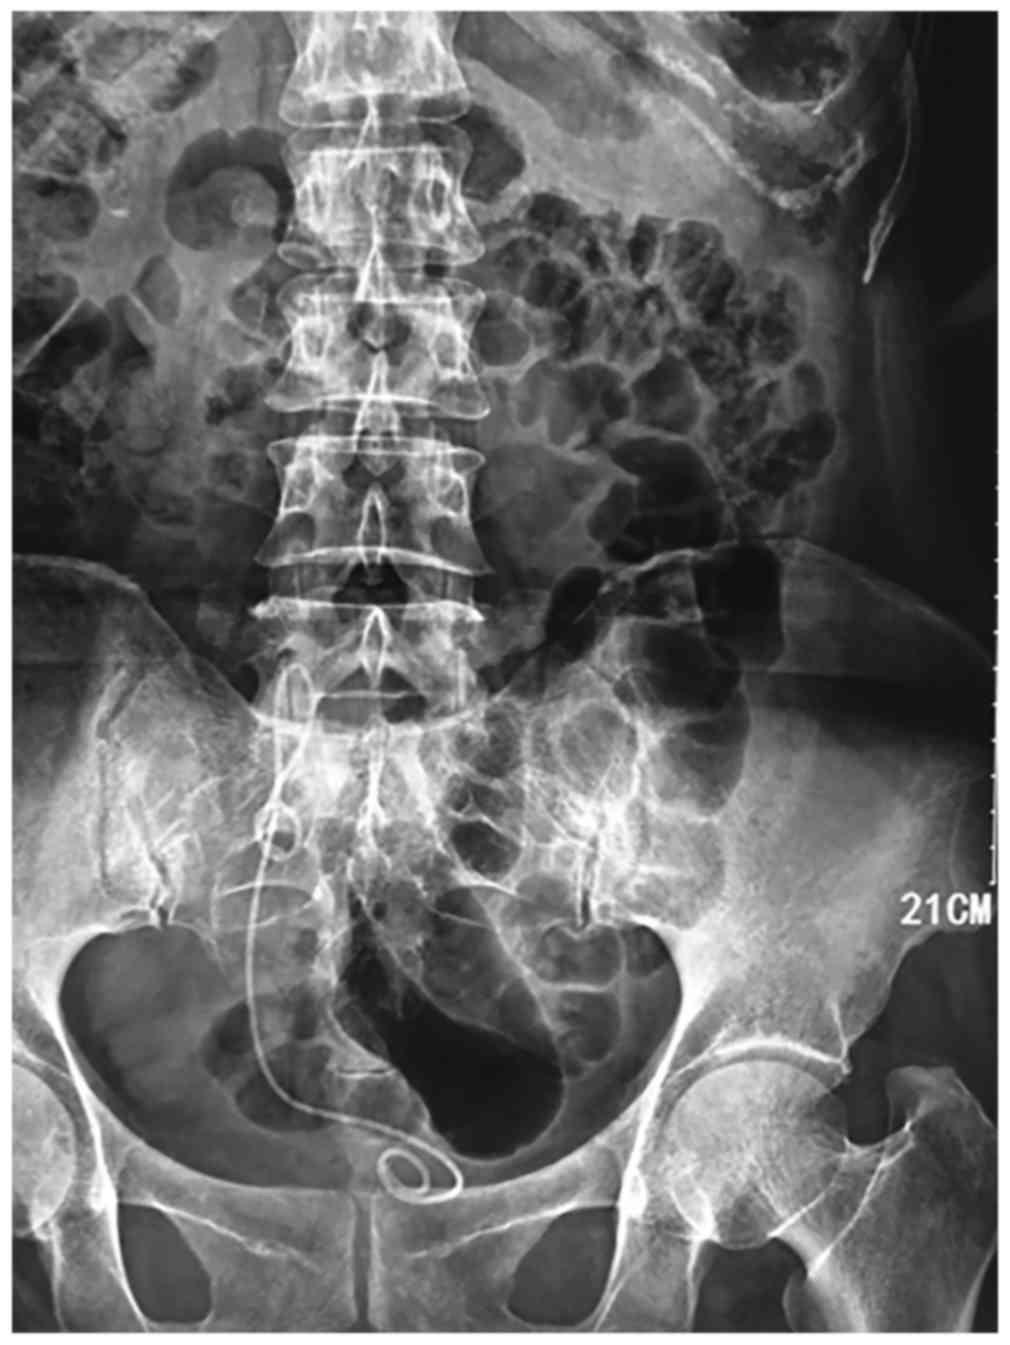

A 53-year-old woman was admitted to the Second Clinical Hospital of North Sichuan Medical College (Nanchong, China) with gross painless hematuria for ~2 years and frequency of urination for ~1 month. The physical examination was unremarkable. Multidetector computed tomography urography (CTU) revealed a filling defect in the lower part of the right ureter (Fig. 1). Cystoscopy revealed a mass ~3 cm in length, with a smooth surface, protruding from the ureteral orifice into the bladder (Fig. 2). Examination of a bioptic specimen suggested that the mass was an inflammatory polyp. A 5F ureteral catheter was inserted from the right ureteral orifice; ~10 cm after the insertion point, resistance was encountered and the catheter could not be advanced further. Retrograde urography was subsequently performed and the contrast media failed to reach the upper part of the ureter and the renal pelvis, whereas the lower part of the ureter exhibited a filling defect (Fig. 3).

Figure 1.

Computed tomography urography showing a filling defect at the lower part of the right ureter.